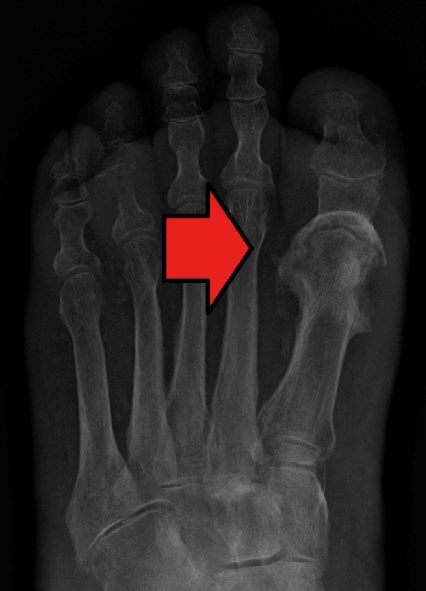

• Serial plain X-rays of the foot:  all non-superficial diabetic foot infections should be assessed with serial plain X-rays with intervals of 2 weeks or more between X-rays to identify bone abnormalities (e.g., deformity, destruction) as well as soft tissue gas and radiopaque foreign bodies [70][72].

• Radiographs tangential to the bone surface at the site of suspected bone infection are ideal to visualize a potential focus of osteomyelitis, in addition to the standard radiographs of the region. Single plain X-rays have low sensitivity and specificity for diagnosis osteomyelitis but serial plain X-rays obtained with an interval of at least 2 weeks are more likely to predict the presence of osteomyelitis [70]. The classical radiologic sign of osteomyelitis is focal loss of bone density, almost always adjacent to the ulcer bed (Figure 13) [40]. Characteristic features of osteomyelitis on plain X-rays of the foot are summarized in Table 6.

Figure 13. Osteomyelitis of the first metatarsophalangeal joint [111]

• Plain X-ray:  Useful to determine location - the most commonly affected joints in Charcot arthropathy are in the midfoot region (ie, the cuneiform/metatarsal area) [12] (Figure 22 and 23).

Figure 22: Charcot foot. X-rays of the same foot, showing progression of disease over 2 years. Fractures in the cuneiform/metatarsal area [120].

Figure 23: Osteomyelitis of the first metatarsophalangeal joint [111]